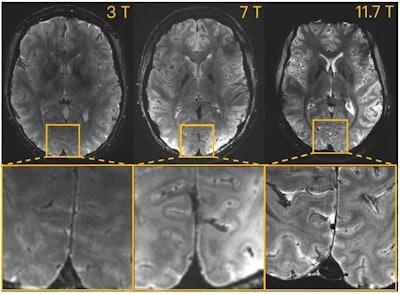

T2*-weighted 2D GRE axial images acquired at 3T, 7T, and 11.7T (different subjects). Acquisitions were performed with resolution = 0.2 × 0.2 × 1 mm3, FA = 27°, TE = 20 ms, TR = 0.6 s, bandwidth = 40 Hz/pixel, acquisition time = 4 min 20 s.